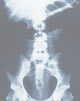

das toxische Megacolon (=vor einer entzündlichen Verschwellung der Darmlichtung im S-Darm oder an der haarnadelförmigen linken Flexur kommt es zu einer Stauung des Darminhaltes mit massiver Aufweitung der Darmschlinge: in schweren Fällen platzt (perforiert) der Darm und es bildet sich eine gefährliche Bauchhöhlenentzündung); » A45